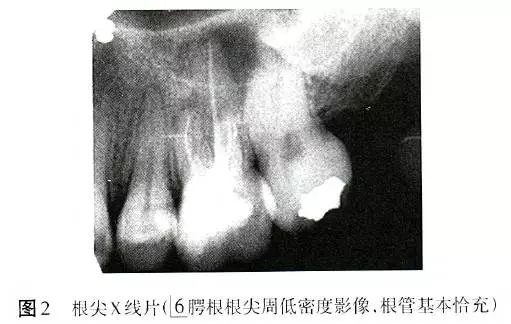

X線片顯示6根管恰充,腭根根尖周低密度影像,直徑6mm×6mm(圖2)。為排除根折,拍攝錐形束CT(CBCT),除發(fā)現(xiàn)MB2遺漏且未見明顯根折以外,意外發(fā)現(xiàn)6根尖周骨病損范圍遠(yuǎn)較X線片所顯示的更廣,累及全部牙根,且患牙頰側(cè)硬骨板缺損(圖3)。診斷:6根管治療后疾?。╬ost-treatment endodontic disease,PTED)。